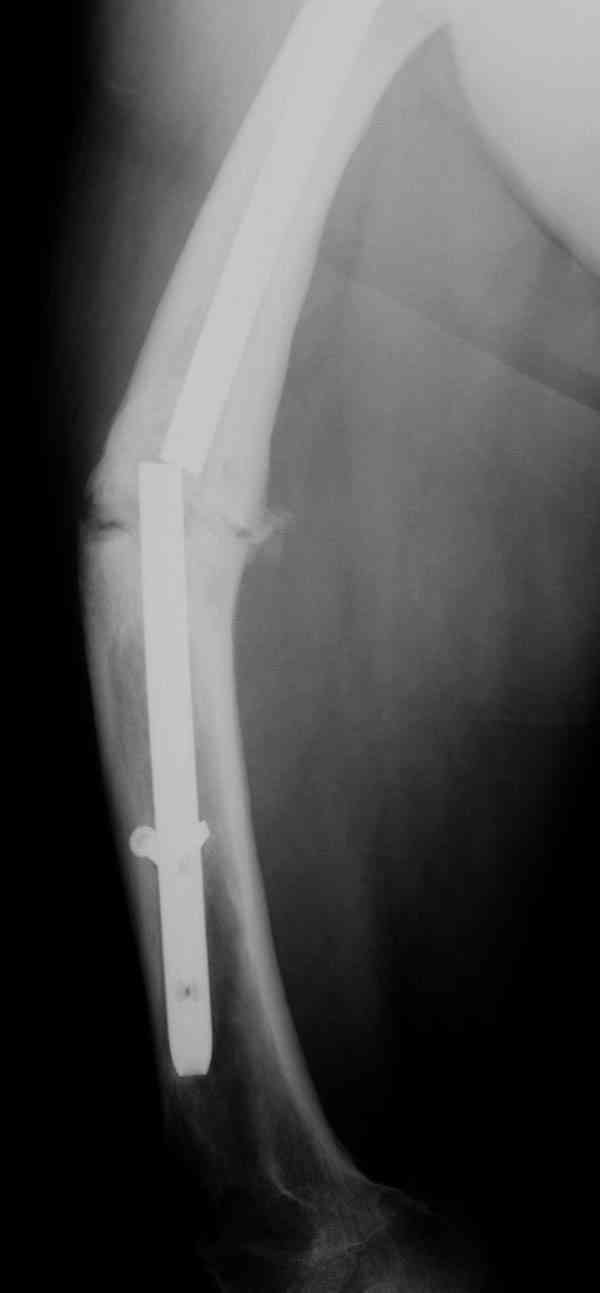

Сросшаяся малоберцовая как распорка привела к образованию ложного сустава. В таких случаях удаляем сломанный штифт и проводим стимуляцию ложного сустава рассверливанием. Рассверливание канала создает стимуляцию на месте ложного сустава, и динамический вариант блокировки штифта с большим диаметром создаст стабильность. Ранняя нагрузка после остеотомии малоберцовой приведет к сращению ложного сустава.

Приспособление для удаления сломанных штифтов и наличие ЭОП облегчит задачу. При отсутствии крючка тогда можно применить обычный длинный ball pointed guide wire от интрамедулярного набора. Проволока, пропущенная за пределы гвоздя и зажатая другая вытащат сломанный конец штифта без проблем.